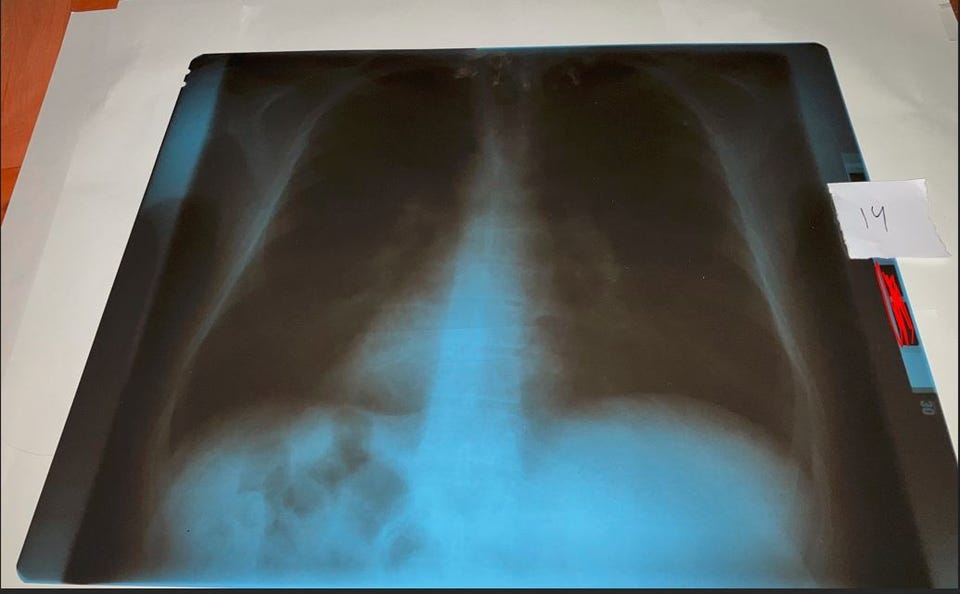

Kuva 14: Etukuva keuhkoista. Koko 43 x 35 cm.